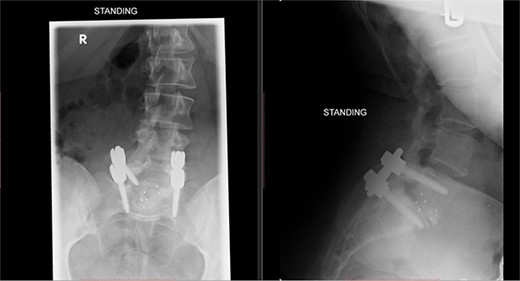

X-rays of the lumbar spine (Fig. 1) and pelvis performed in December 2015 showed a small idiopathic scoliosis in the lumbar spine. A magnetic resonance imaging (MRI) scan was performed in February 2016, which showed non-compressive disc degeneration and disc bulge at L4/5 and L5/S1. She was referred to physiotherapy for rehabilitation.

Preoperative X-ray of the lumbar spine performed in December 2015, confirming small idiopathic scoliosis in the lumbar spine.